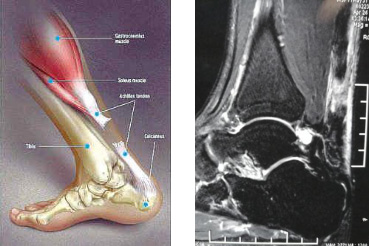

跟腱断裂通常在30~50岁的男性患者中发病率较高,平均年龄约35岁,其发病率在发达国家为每年每2~10/10万人,男女发病比例约为4:1至20:1。跟腱断裂在人体肌腱断裂部位发生率位居第三位。患者常诉有足跟后方有棒击感,随即出现提踵无力,无法完成蹬地、跳跃等动作,表现为行走困难及推进无力并伴有跛行,跟腱处出现凹陷。最易明确诊断的检查方法是通过挤压小腿后方肌肉来判断腓肠肌-比目鱼肌复合体的连续性,即Thompson征阳性。怀疑跟腱断裂的患者,可通过B超或MRI检查来明确。

跟腱断裂示意图 跟腱断裂MRI表现

患者于某,因打球致左足跟部疼痛肿胀1天入院,查体左足跟部肿胀,按之空虚感,Thompson试验阳性,左足跖屈无力。既往体健。MRI显示左跟腱断裂(见上图)。入院后,完善检查后,给予左跟腱断裂微创修复术,术中情况见下图,术后踝关节跖屈位短腿石膏固定6周,更换跟腱靴6周后正常下地活动。未见并发症发生,患者非常满意。